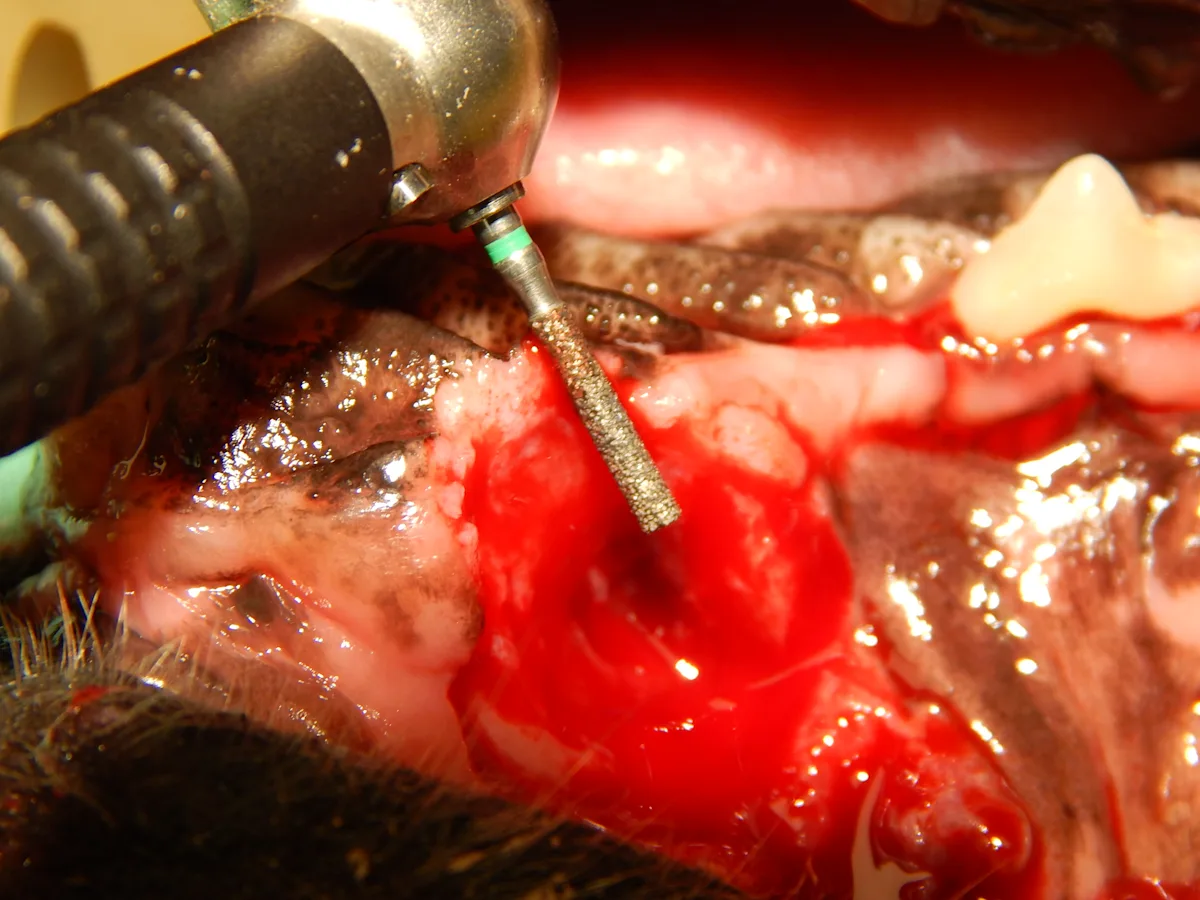

A coarse cylindrical diamond bur used to create a recipient bed (A). Removal of the epithelium allows improved healing of the sutured mucogingival flap (B).